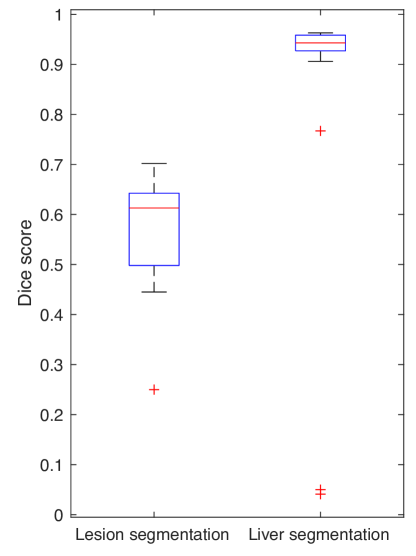

For test on the LiTS challenge volumes, the lesion segmentation dice score is 0.586 while for the liver it reaches 0.938.

For comparison, Figure 3.12 and Table 3.1 present the challenge results. The first position was occupied by the Lenovo Research team.

| Dice score\Quantile | 0.025 | 0.25 | 0.5 | 0.75 | 0.975 | Best |

|---|---|---|---|---|---|---|

| Lesion | 0.289 | 0.498 | 0.613 | 0.643 | 0.699 | 0.702 |

| Liver | 0.043 | 0.927 | 0.943 | 0.959 | 0.967 | 0.963 |